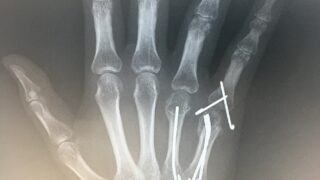

右手薬指及び小指の中手骨骨折する前の演奏動画